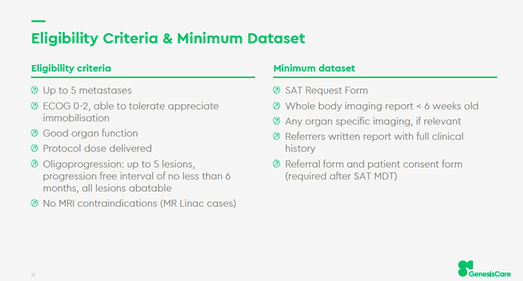

The role of stereotactic ablative radiotherapy (SABR) as a single therapy or part of a combined approach in the treatment of metastatic cancer is steadily evolving.

Data from studies such as the SABR COMET phase II trial and the NHS England Commissioning Through Evaluation scheme has shown very encouraging results. In patients with extracranial oligometastatic disease the use of SABR was associated with both an increase in survival but also low toxicity.

In the UK GenesisCare provides both ‘simple’ and ‘complex’ SABR treatments. Simple SABR means non-spine bone, peripheral lung, and pelvic lymph node metastases. It is available at all UK GenesisCare centres.

Complex SABR means spine, liver, pancreas, central lung, abdominal nodes and reirradiation and is available at centres where local expertise is available, and demand requires it. In addition, SABR is also available using the MR Linac with daily adaptation in both Oxford and the Cromwell Hospital for challenging anatomical locations.

All consultants who have attended the GenesisCare Credentialing Programme, or who can demonstrate relevant experience in the NHS can refer and treat simple SABR cases. To date approximately half the cases treated across the UK GenesisCare network have been ‘simple’.